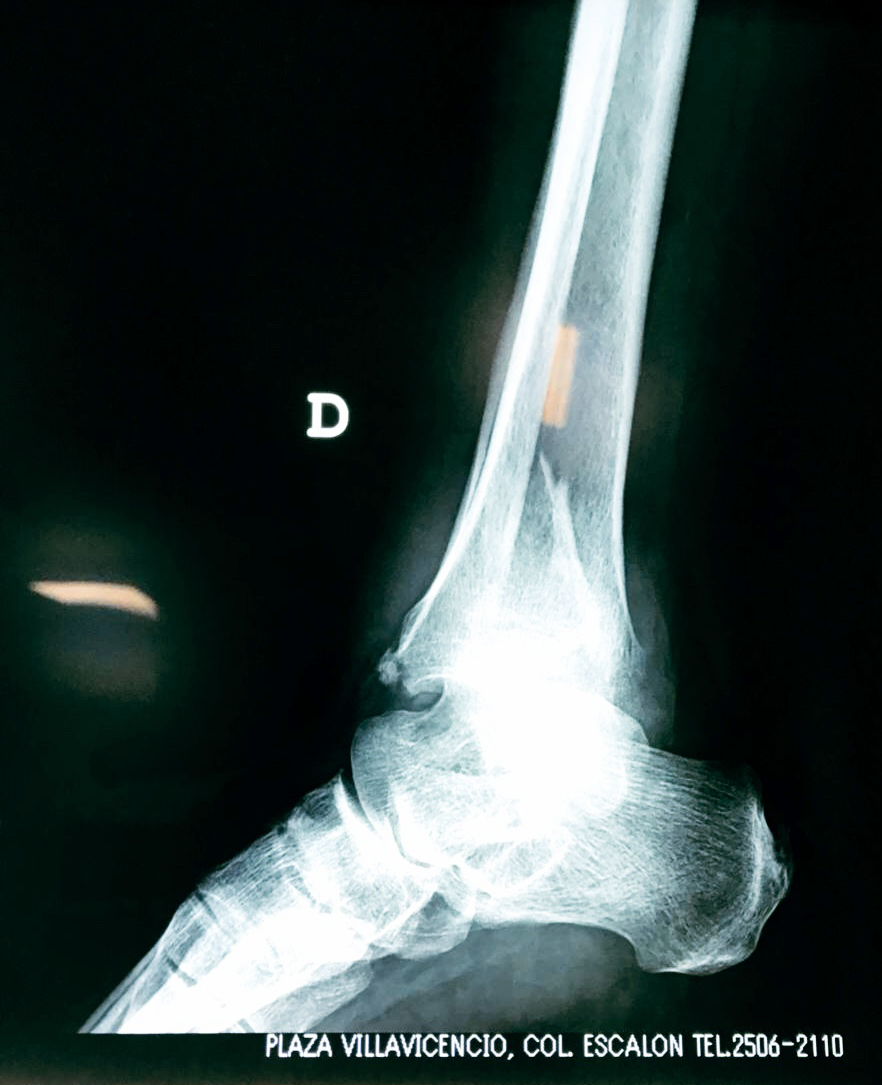

Una fractura de tobillo es la rotura de uno o más de los huesos del tobillo. Estas fracturas pueden ser:

- Parciales (el hueso está sólo parcialmente fisurado, no del todo).

- Completas (el hueso está perforado y está en 2 partes).

Algunas fracturas de tobillo pueden requerir cirugía si:

- Los extremos de los huesos están desalineados entre sí (desplazados).

- La fractura se extiende hasta la articulación del tobillo (fractura intra-articular).

- Los tendones o ligamentos (tejidos que sujetan los músculos y los huesos entre sí) están rotos.